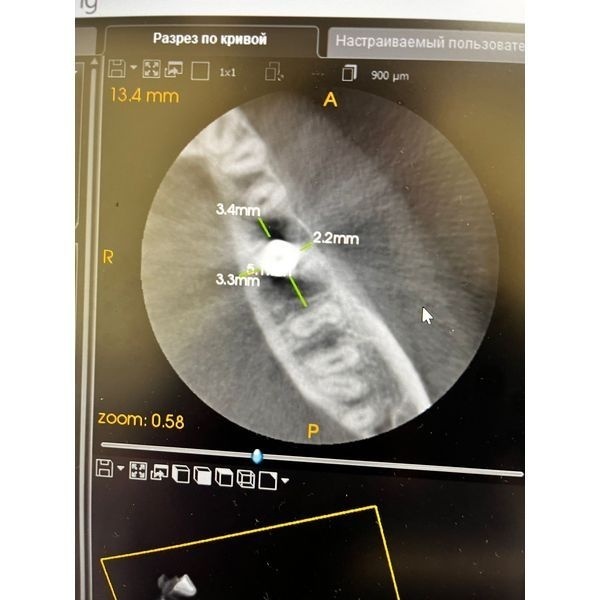

КТ нижней челюсти показала:

- ширина в планируемом месте постановки имплантата приблизительно 10 мм;

- высота до нижнего альвеолярного нерва — 14 мм;

- расстояние между зубами 3.5 и 3.7 — 13 мм.